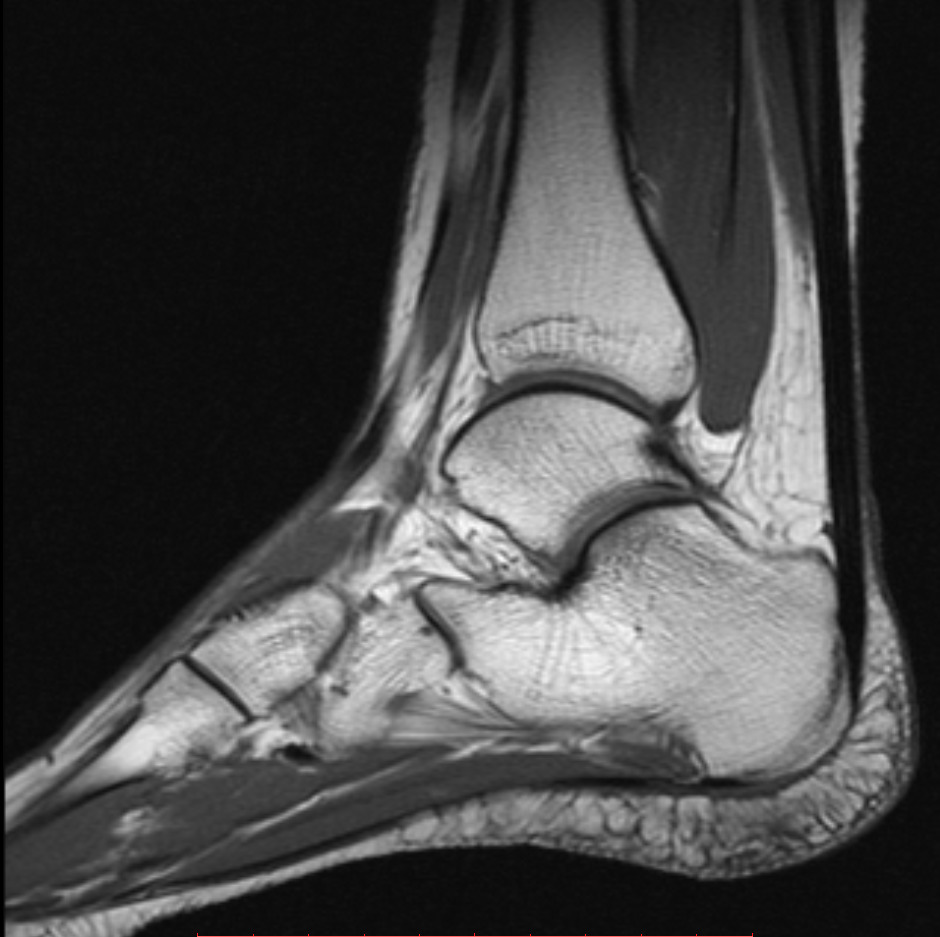

МРТ голеностопного сустава - это высокоинформативный диагностический метод, который используется при воспалительных, опухолевых, а также дегенеративных поражениях. Он является наиболее предпочтительным при заболеваниях и травмах голеностопа, так как максимально точно определяет локализацию и причину патологии.

МРТ голеностопного сустава с контрастом дает возможность получить высококачественные трехмерные изображения. Достигается это при выполнении исследования на современном высокопольном оборудовании компании Сименс с мощностью 1,5 Тесла. Данные томографы позволяют хорошо рассмотреть связки, костную ткань, синовиальную оболочку, мышцы и хрящи. Также процедура эффективна для оценки кровообращения, выявления степени запущенности онкологического образования.

Врачи при этом имеют возможность получать снимки с толщиной среда 3 мм. Подобной точности пока не имеет ни один другой диагностический метод.